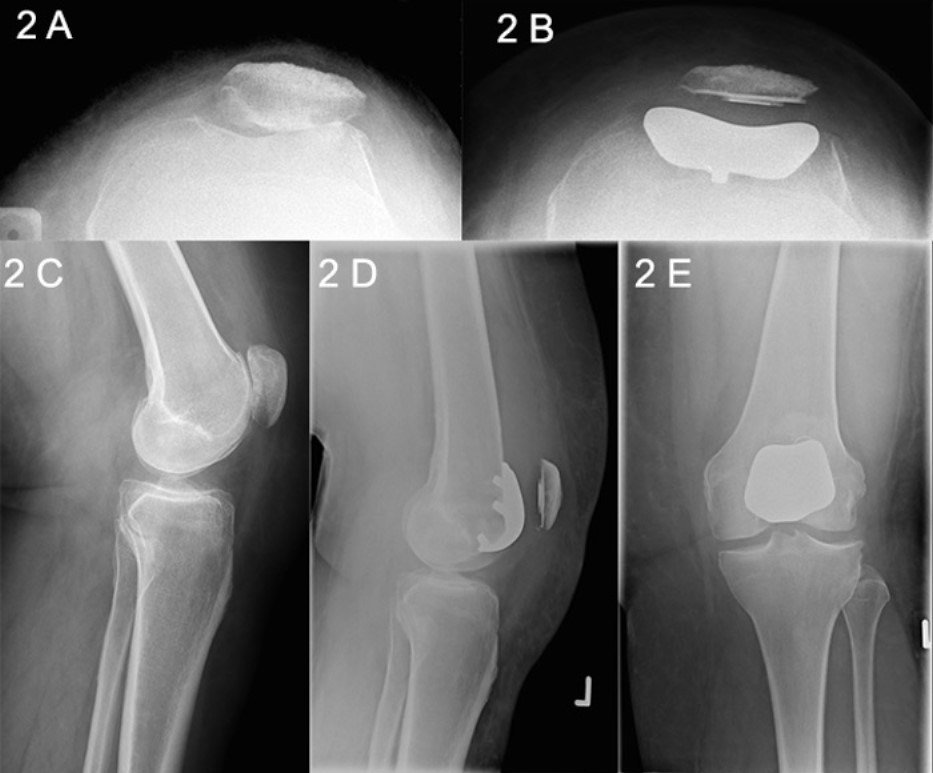

Clinically, patients will often have tenderness around the patellofemoral region, often associated with signs of chronic patellofemoral maltracking. Signs of a ligamentous laxity syndrome are often found. Imaging studies used will include Xrays, MRI scans (to confirm the medial and lateral compartments are not involved), and occasionally CT scans.

The ideal patient for patellofemoral joint replacement is one with severe signs and symptoms of isolated patellofemoral compartment arthritis, correlated with X-ray proven arthritis, and with essentially no changes in the medial or lateral knee compartments (may need MRI scans to confirm), and for which nonsurgical treatment options are no longer giving adequate relief of symptoms.

A/Prof Woodgate performs a diagnostic knee arthroscopy for all the patients before the actual skin incision to confirm suitability for the procedure, that is, isolated patellofemoral arthritis and rest of the knee is essentially normal. If damaged cartilage is found in other areas of the knee, the patellofemoral arthroplasty is not performed. A contingency plan will have been discussed with you prior to surgery to make sure that you agree with alternative strategies, either arthroscopic debridement or a total knee replacement.